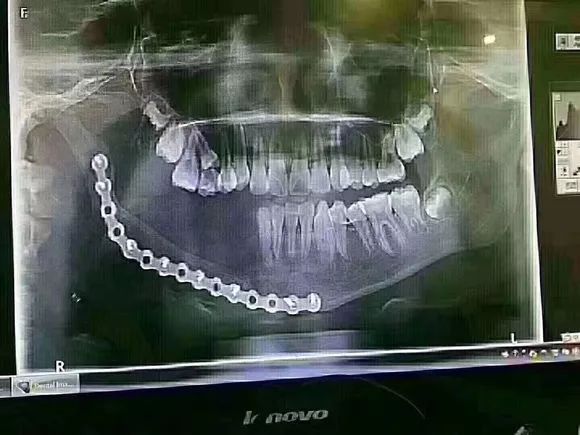

北京一个12岁的孩子,因乳牙过早龋坏,太严重引起下颌大面积囊肿没办法治疗,做了下颌骨切除手术,缺失半侧恒牙,这一生要做无数次假牙!而且孩子面部发育也会受到很大的影响!

先看这位9岁孩子的牙片

这是一位9岁的小姑娘,因父母没有重视乳牙护理和龋齿治疗,那颗乳牙下面的颌骨大面积吸收!当然,囊肿造成的乳牙根尖周炎,也可能是这种吸收的可能原因之一(由于没有详细资料和医生的诊断)。